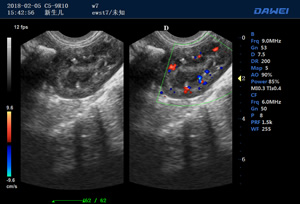

·支持B、C、PW、CW、寬景成像

·適用于各種動物的臨床腹部、胸腔,心臟、肌腱、小器官、眼球、生殖系統等的檢查